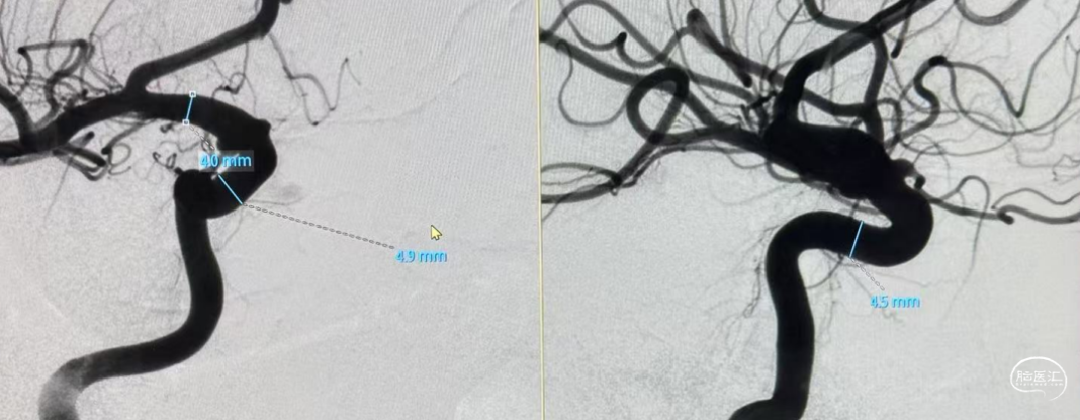

CTA:右侧颈内动脉C6段动脉瘤。

DSA:DSA提示右侧颈内动脉C6段可见多发动脉瘤。

术前诊断:右侧颈内动脉C6段多发动脉瘤。

载瘤动脉远端血管直径:4.0mm

载瘤动脉近端血管直径:4.9mm、4.5mm(两个角度)